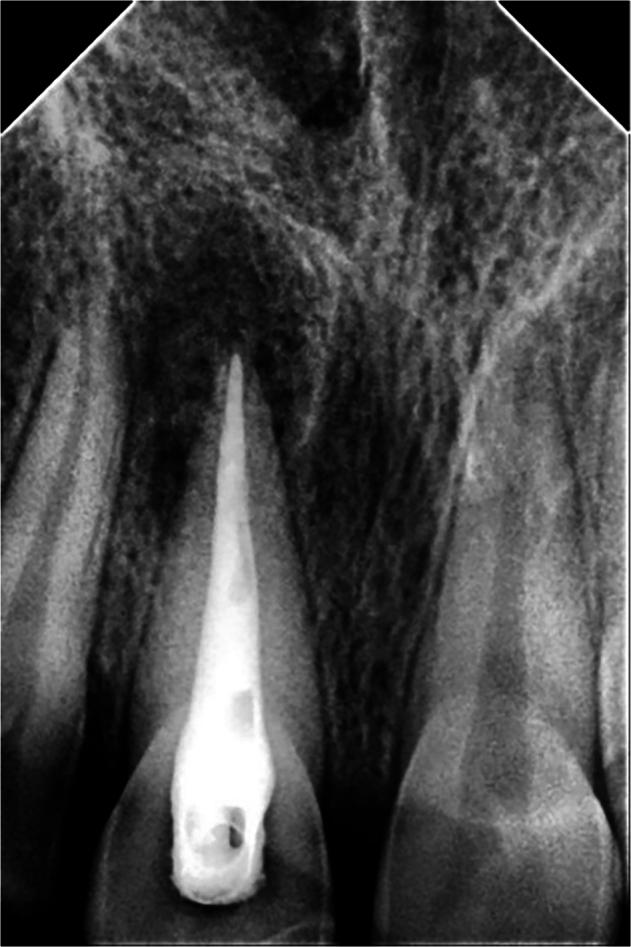

A randomized controlled trial was conducted on 41 patients who had 60 permanent teeth in the maxillary incisors that were accompanied by large-sized periapical lesions. The included teeth were radiographed with cone beam computed tomography (CBCT) images and divided equally into two groups according to the endodontic treatment statute (30 untreated previous cases and 30 retreated cases). Subsequently, teeth received uniform preparation, irrigation, and dressing procedures. Then each group was divided equally according to the used sealer (15 teeth obturated using AH plus sealer with LCT and 15 teeth obturated using BC sealer with SCT). All cases were followed up after 6 and 12 months with CBCT images. Subsequently, the change in periapical lesion diameter (PLD) was observed as an indicator to determine the treatment outcome score. One-way ANOVA and Mann-Whitney U test were used to analyze the PLD changing and scoring the treatment outcome during the follow-up periods. The significance level was set at α = 0.05.

对41例上颌切牙有60颗恒牙且伴有大型根尖周病变的患者进行了一项随机对照试验。纳入的牙齿用锥形束计算机断层扫描(CBCT)成像进行放射照相,并根据牙髓治疗情况平均分为两组(30例既往未治疗病例和30例再治疗病例)。随后,对牙齿进行统一的预备、冲洗和换药程序。然后根据所用封闭剂将每组再平均分为两组(15颗牙齿使用AH plus封闭剂和LCT进行根管充填,15颗牙齿使用BC封闭剂和SCT进行根管充填)。所有病例在6个月和12个月后用CBCT图像进行随访。随后,观察根尖周病变直径(PLD)的变化作为确定治疗结果评分的指标。采用单因素方差分析和曼-惠特尼U检验分析随访期间PLD的变化及治疗结果评分。显著性水平设定为α = 0.05。